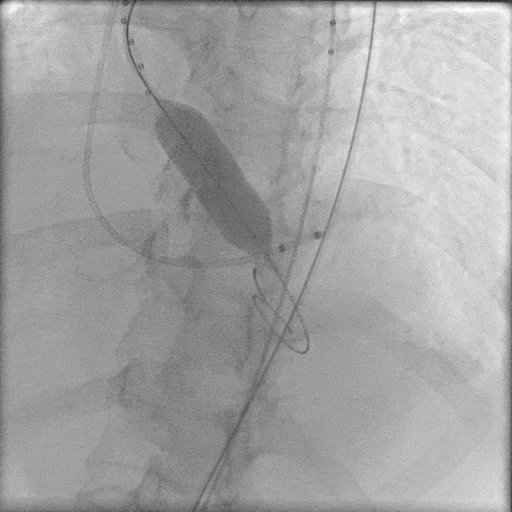

主动脉根部造影,主动脉狭窄伴有明显反流,采用18mm球囊预扩,轻微腰征,造影无漏。

主动脉根部造影

球囊预扩

TaurusElite 输送器轻松过弓、跨瓣,LAO 11° CRA 15°投照角度下,第一次定位。

TaurusElite轻松过弓

第一次定位

第一次释放后,造影评估深度偏深,随即完全回收。

第一次释放

第一次回收

由于患者本身是Type0型二叶瓣,加上钙化较重,给瓣膜植入的位置增加了难度,术中释放多次释放部分回收后,最终释放一个比较满意的位置。

最终定位

最终释放

瓣膜稳步脱钩后,造影显示瓣膜位置合适,冠脉灌注良好,无瓣周漏。

稳步脱钩

最终造影